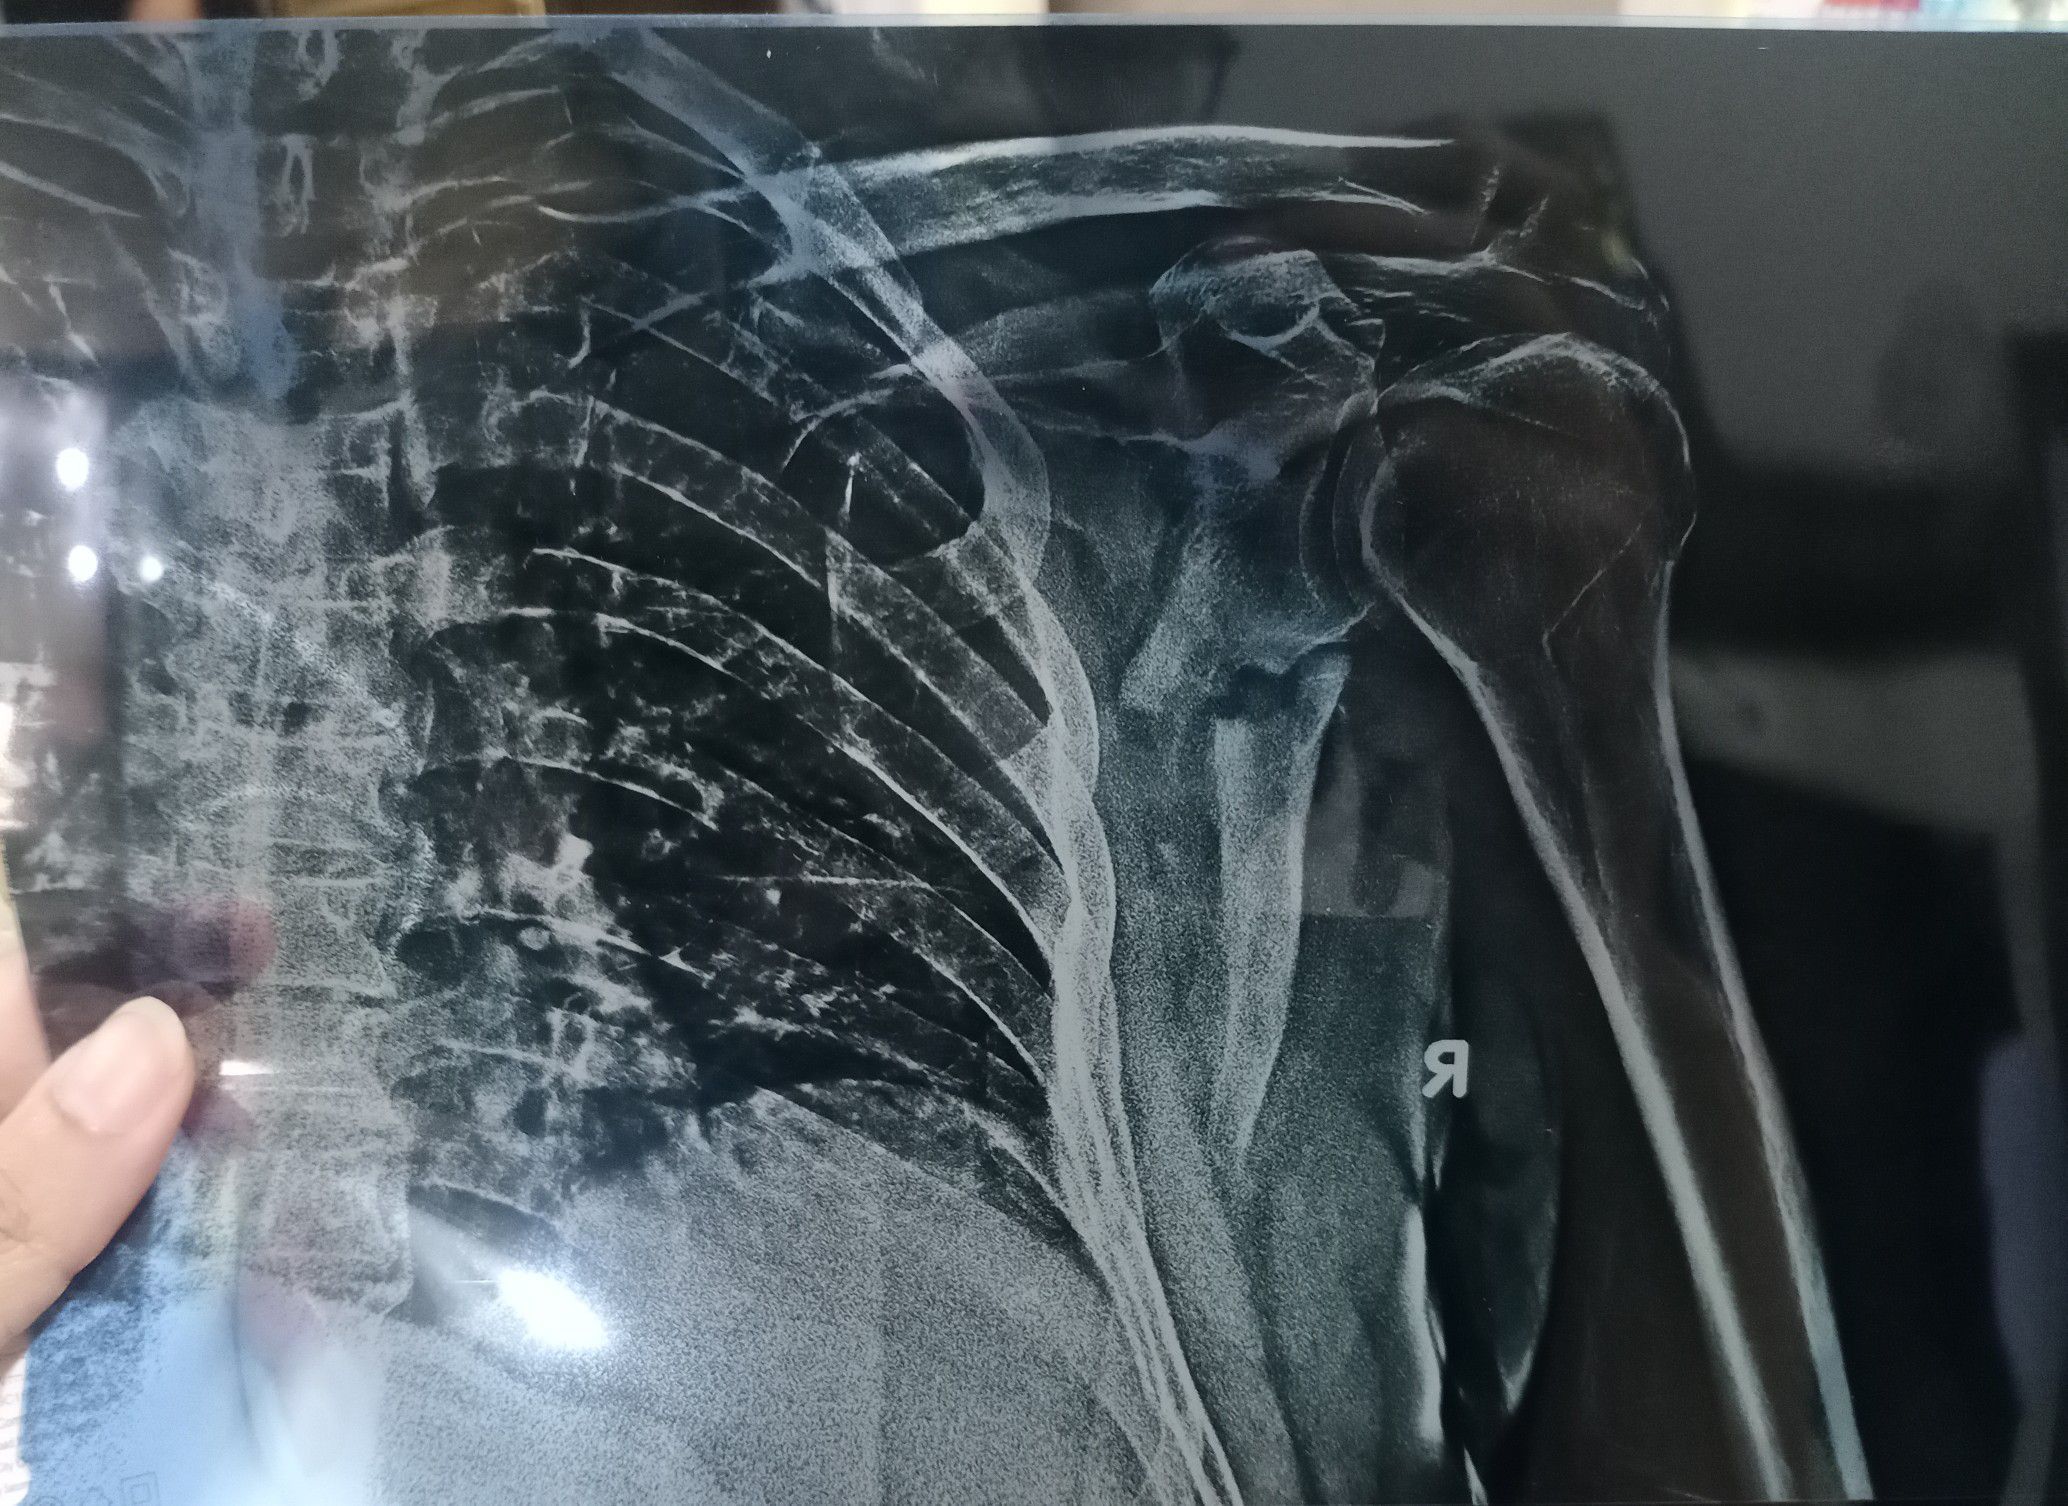

X-ray showing displaced fracture passing through the body of scapulae. Most scapular fractures are managed conservatively by applying poly sling, ice packing, and pain management. Acromion, glenoid cavity fracture , fracture of neck of scapulae, associated life threatening fractures like clavicle or rib fracture leading to pneumothorax or emphysema usually require surgical management.